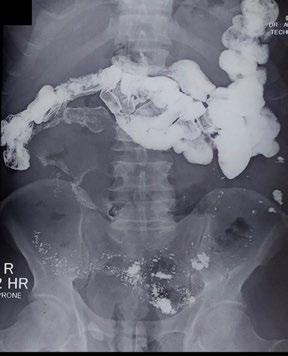

A Proposal for a New Fluoroscopy Severity Assessment in Achalasia: The In Vivo Assessment of Achalasia Score

Citation: EMJ Radiol. 2024;5[1]:25-26. https://doi.org/10.33590/emjradiol/NMKL9036.

BACKGROUND AND AIMS

The aim of the study was to establish a quali-quantitative fluoroscopic severity assessment for achalasia, comparable to the equivalent clinical Eckhard scoring system (ESS).

MATERIALS AND METHODS

From September 2020–August 2022, 69 patients already diagnosed with achalasia, and scored with ESS, were recruited and evaluated with the authors’ fluoroscopy barium protocol. The anteroposterior (AP) sequence was used to divide the oesophagus into nine segments, according to Brombart's classic description, plus the gastro-oesophageal junction. Three scoring items were chosen, after a profiling study of achalasia, to depict the features, some mutually exclusive, of the three clinical subtypes: lumen dilation, stasis, and spasm. Each oesophageal segment was scored for the three items (1 point given if the item was present; 0 points given if no item). The In Vivo Assessment of Achalasia (IVA) score was calculated by summing points up, until a maximum of 20 points for each subtype was reached. IVA scores were then normalised on a 0–12 scale to be compared to ESS.

RESULTS

IVA and ESS scores were not found to be statistically diverging in 60/69 patients (86.95%; p=0.05). IVA scores were diverging, and superior to ESS in 6/69 patients (8.69%); in this group of patients, the ESS 'chest pain' and 'weight loss' items were found to be biasing factors. IVA scores were inferior to ESS in just 3/69 patients (4.34%). In all patients with a diverging IVA score (9/9), ESS scores were found to be lower than 6/12.

CONCLUSION

IVA score was found to be consistent and compatible with ESS scores, especially in patients with moderate-to-severe achalasia.

The apparent superiority of imaging scores in a small proportion of patients might instead be used as a revealing tool to call out patients in which the ESS does not reflect the disease's severity, due to internal biases. ●